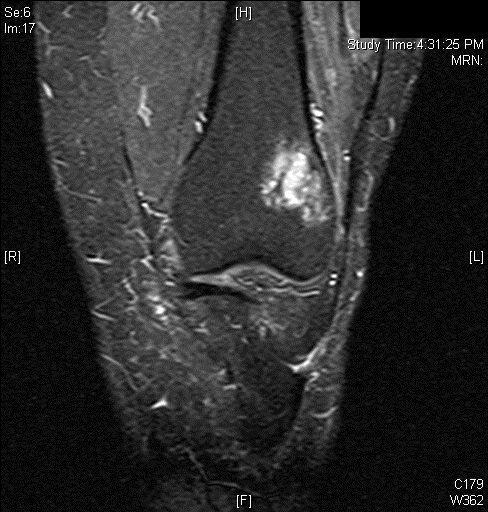

MRI

• MR Imaging, demonstrates intermediate to hypointense signal on T1-weighted images (Fig. 4 & 5) and hyperintensity on T2-weighted images (Fig. 6 & 7).

• Most cases show an extraosseous mass and cortical disruption on MRI.

Fig. 6

Fig. 7

Fig. 6 & 7: MR Imaging. Axial (Fig. 6) and Coronal (Fig. 7) T2 fat saturated image demonstrating T2 hyperintense lesion within the lateral supracondylar femur with a small amount of surrounding bone marrow edema.